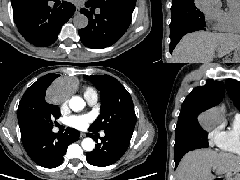

纵隔大细胞神经内分泌癌1例CT影像

纵隔大细胞神经内分泌癌1例CT影像  张力性纵隔气肿影像表现及严重度分级